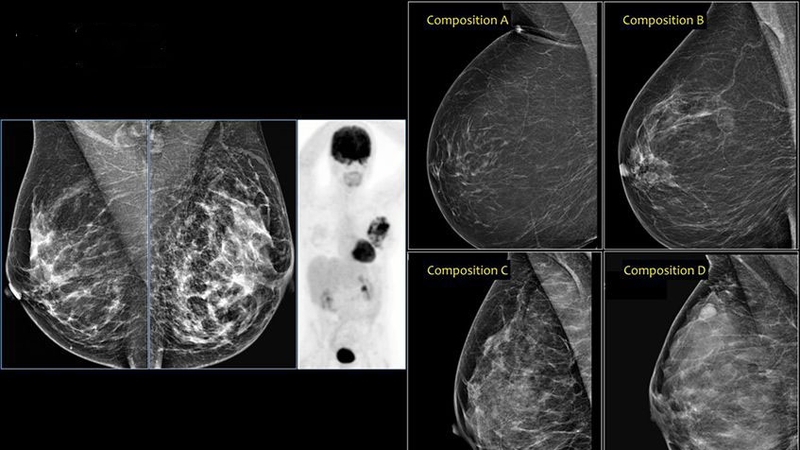

Phân loại BIRADS là một hệ thống tiêu chuẩn được các bác sĩ X-quang sử dụng để phân loại các kết quả hình ảnh vú. Hệ thống này giúp đánh giá nguy cơ ung thư vú và hướng dẫn các bước tiếp theo trong quản lý bệnh nhân. Dưới đây là giải thích chi tiết về từng loại BIRADS và ý nghĩa của nó đối với bệnh nhân:

Loại sang thương vú BIRADS 2 cho thấy sự hiện diện của một hoặc nhiều tổn thương lành tính ở vú. Các dấu hiệu lành tính thường gặp bao gồm vôi hóa, khối u lành tính, hạch bạch huyết ở vú, u mỡ, u nang dầu và khối u có mật độ hỗn hợp. Mặc dù những tổn thương này không phải là ung thư nhưng việc kiểm tra ung thư thường xuyên vẫn nên tiếp tục theo khuyến nghị của bác sĩ.